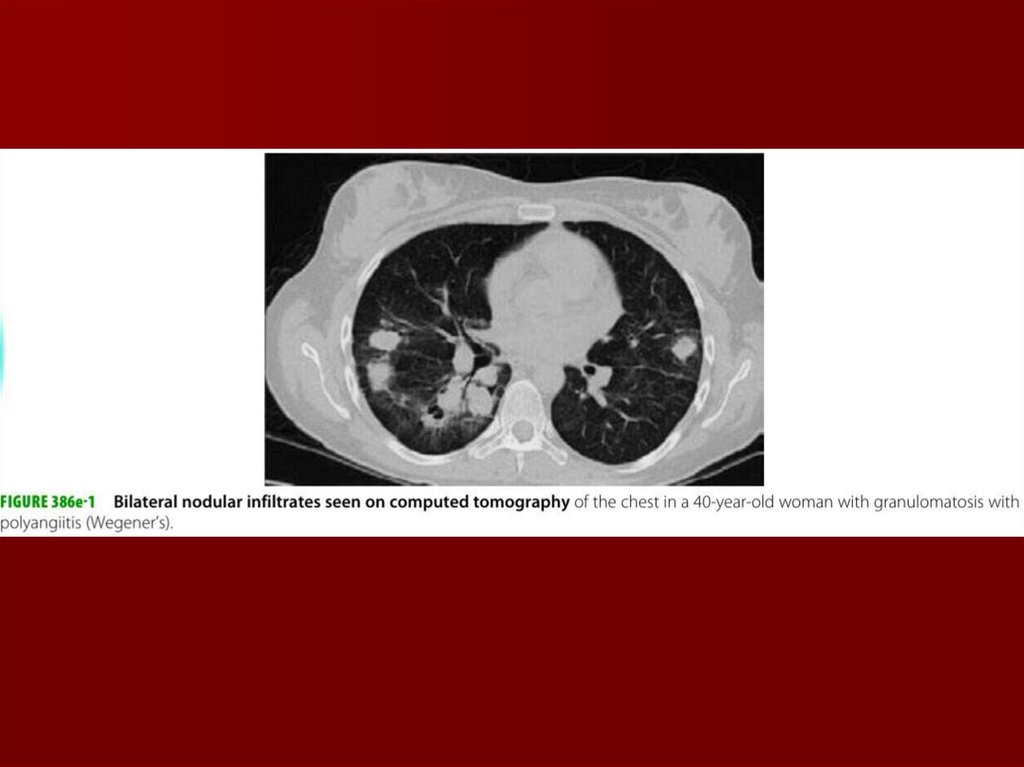

39. Диагностика